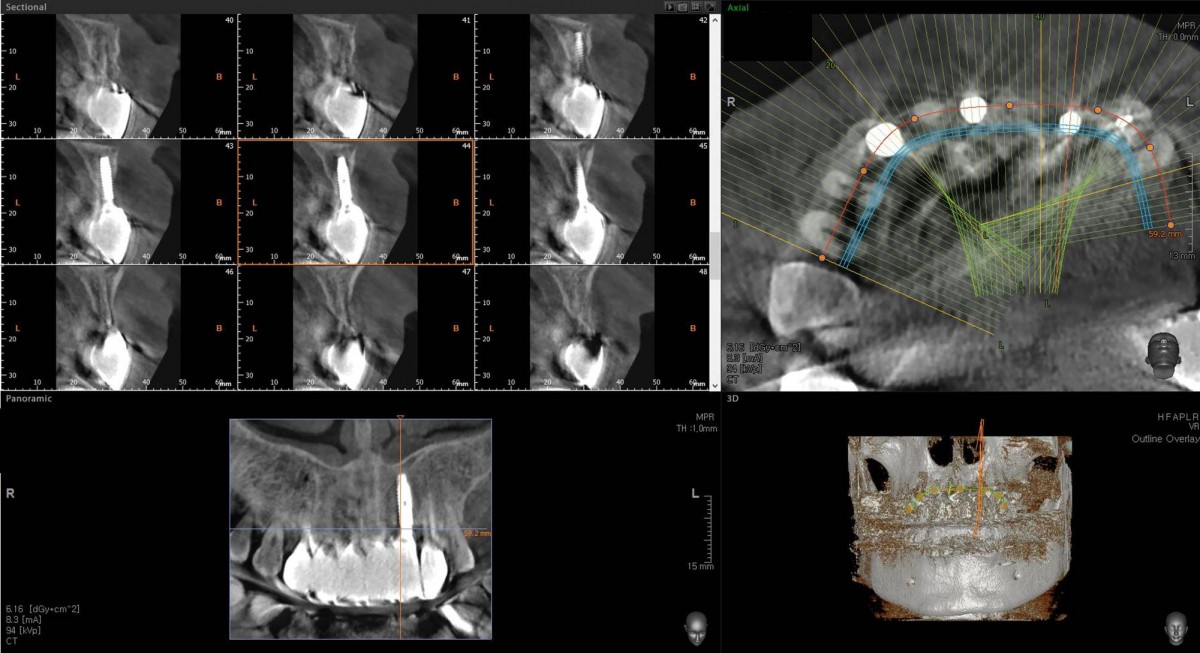

<GCpbc> A 58-year-old male is a patient undergoing implant installation in various parts. The old Br of the anterior maxilla has fallen

off and it is no longer possible to maintain it even temporarily, so a

treatment plan for the anterior teeth was made.